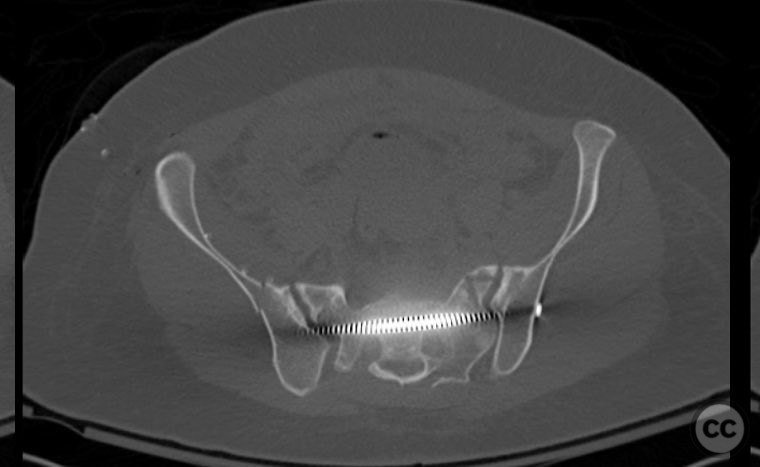

Clinical Details

Clinical and radiological findings:  A 26-year-old female sustained a closed pelvic ring injury following a motor vehicle accident. She was hemodynamically stable, neurologically intact, and had no other associated injuries. Skin integrity was preserved. Initial management included pelvic binder application and 10 pounds of distal femoral skeletal traction. Portable AP pelvic radiograph demonstrated a left-sided sacral fracture with associated ipsilateral iliac wing and pubic ramus fractures, consistent with an AO/OTA 61-B2 (lateral compression type II) injury pattern.

Anatomical surgical approach:  The left sacral fracture was addressed first via percutaneous placement of iliosacral screws under fluoroscopic guidance. An anterior approach to the iliac wing was performed via a longitudinal incision along the crista iliaca, subperiosteal dissection to expose the fractura alae ossis ilii, followed by debridement, reduction, and temporary clamping. Definitive fixation was achieved with two 7mm diameter cannulated fully threaded medullary screws placed across the iliac crest and pelvic brim into the corpus ossis ilii. The left ramus ossis pubis fracture and overall cingulum pelvicum were assessed intraoperatively with fluoroscopy for residual instability.

Intraoperatively, minimal residual deformity of the left hemipelvis was noted after traction and positioning. The sacral fracture was stabilized first with iliosacral screws. The anterior iliac exposure allowed for direct visualization, cleaning, reduction, and clamping of the iliac wing fracture prior to screw fixation. After fixation, intraoperative fluoroscopic stress examination demonstrated stability of the left pubic ramus fracture and overall pelvic ring, obviating the need for further anterior fixation.

Orthopaedic implants used:   Two 7mm diameter cannulated fully threaded medullary screws (iliac crest and pelvic brim), percutaneous iliosacral screw(s).